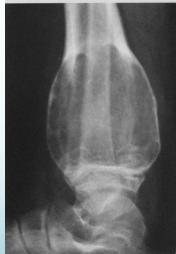

Osteochondroma (Exostosis)

- A common lesion

- Ends of long bone

- Bony overgrowth:

- Away from epiph. plate

- Covered by cartilage

- Growth:

- Stops when epiphysis close

- If continues later:

- ? Malignant transformation

Source: radiopaedia.org, Apley’s System of Orthop. And Fractures